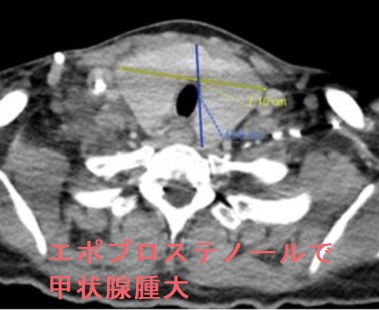

- 甲状腺機能異常を伴わない甲状腺腫大(Case Rep Pulmonol. 2020 Jan 23;2020:1617253.)

- 最初は抗甲状腺薬(メルカゾール、プロパジール、チウラジール)によく反応しても、PGI2 製剤を中止できなければ、治療途中で甲状腺腫(甲状腺の腫れ)が大きくなって再発します。

プロスタサイクリン(PGI2)誘導体(ベラプロスト、エポプロステノール)は、びまん性甲状腺腫を伴う橋本病(慢性甲状腺炎)を誘発する場合もあります。(Lung. 2019 Dec;197(6):761-768.)